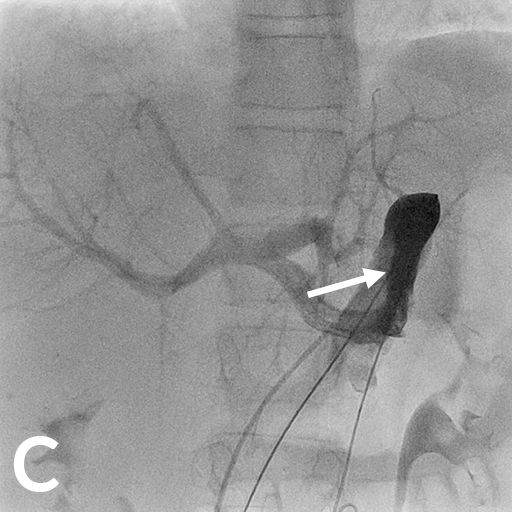

8 jähriger Junge nach Transplantation der linksseitigen Lebersegmente

In der Bildgebung (MRCP-Bild, A) zeigt sich eine Erweiterung der Gallenwege in der Leber, bedingt durch eine Engstelle an der Verbindung der Gallenwege (Gallenwegsanastomose). Entlastung der gestauten Gallenwege mittels PTCD. Punktion eines in der Leber gelegenen Gallenweges mit Hilfe von Ultraschall. Gabe von Kontrastmittel über die Punktionsnadel (B). Darstellung des gestauten Gangsystems und der Engstelle (Pfeil). Anschließende Anlage einer Ableitung (Drainage) zur Entlastung des Gallenwegssystems (C).